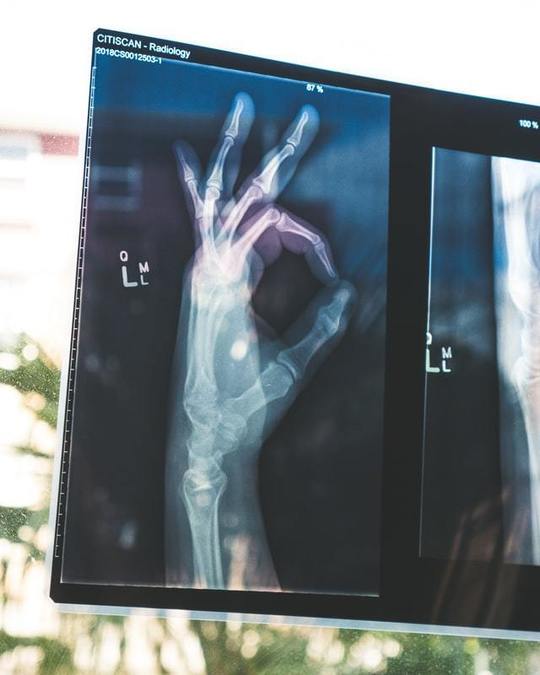

打撲は、強い衝撃を受けることによって起こる筋繊維や血管の損傷

打撲は、衝突や転倒などで強い衝撃を受けることによって起こる筋繊維や血管の損傷のことです。打ち身と言われることもあります。

打撲の程度が軽い場合の症状は、打った部分を圧迫した時に感じる痛みですが、程度が中等度以上になると腫れや熱感のある痛みが起こります。皮膚や皮下組織の血管や筋肉に傷がついて内出血を起こすことも多いです。